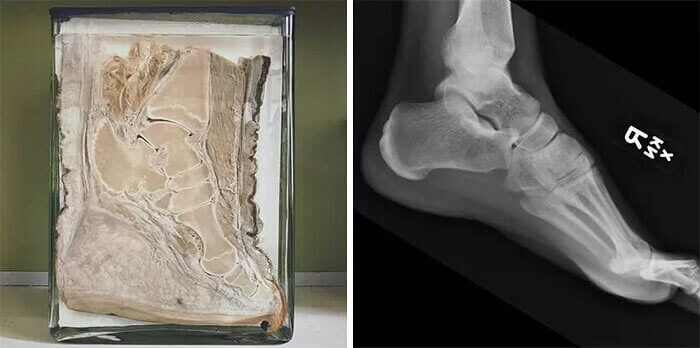

The Gigantic Differences in An Elephant Foot Vs. Human Foot

Just looking at elephants, it's clear that humans are a very different breed. A closer inspection of the feet of each species proves that is true, once and for all. This X-ray shows that Dumbo actually walked on his tiptoes!

A few readers online disputed that this contrast, though. Many researchers say that shoes have totally ruined the way we are supposed to walk. Maybe we have more in common with elephants, despite our denial!